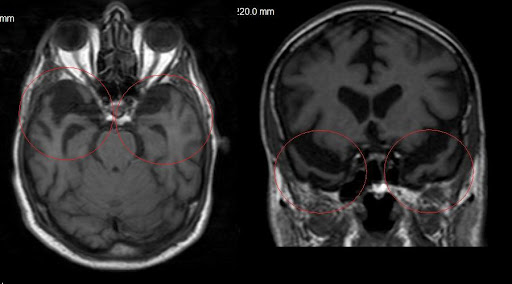

Retinadaki sinir lifi tabakasının kalınlığı daha önce bilişsel performansla ilişkilendirilmişti. Bu çalışmada da sinir lifleri, ganglion hücreleri ve iç pleksiform tabakası mercek altına alındı. Özellikle sinir lifi tabakası önemliydi çünkü görsel sinyalleri beyne taşıyan lifleri içeriyordu.

Ancak bu kez, araştırmacılar retinal mikrodamar sağlığının demans riskiyle daha güçlü bir ilişki gösterdiğini fark etti. Retinada bulunan küçük atardamarların (arteriyoller) daralması ve küçük toplardamarların (venüller) genişlemesi, demans riskinin artışıyla bağlantılı bulundu.

Bu damar yapıları, yalnızca göz sağlığı değil, vücudun genel damar sistemi ve özellikle beyin damar sağlığı hakkında da bilgi sunuyor. Alzheimer’ın gelişiminde damarsal etkenlerin önemli bir rol oynadığı biliniyor.